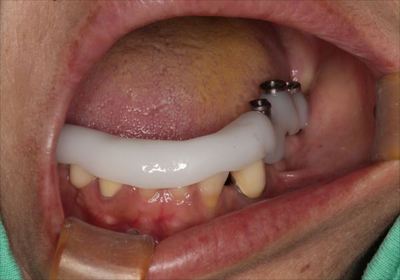

ヒーリングキャップでインプラントのスクリューホールを保護するとともに、

粘膜貫通部の形態の形成、粘膜弁の固定を行います。

![]()

ヒーリングキャップの締結と縫合を終えました。